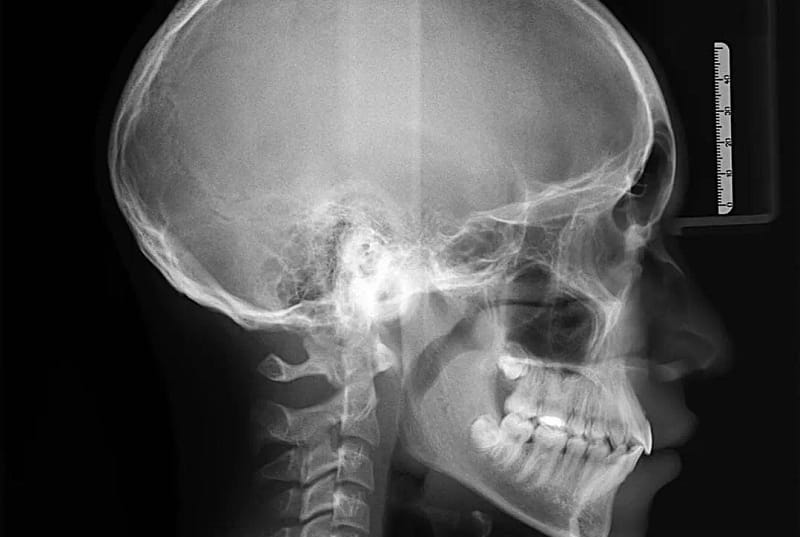

Somos una empresa con más de 5 años ofreciendo servicios de radiología oral y maxilofacial, fotografía intra y extra oral, toma de modelos (estudio y trabajo), análisis cefalométrico por parte de Radiólogos.